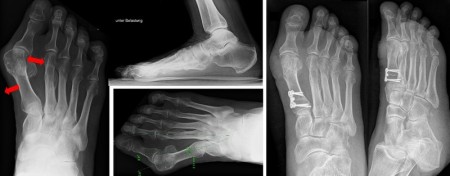

Lapidus-Arthrodese:

Die Versteifung im TMT-Gelenk (der Gelenkverbindung zwischen der Fußwurzel und dem 1. Mittelfußstrahl) ist fortgeschrittenen Fällen vorbehalten, bei denen neben einer Hallux valgus Fehlstellung der Großzehe auch eine erhebliche Lockerung des Bandapparates im inneren Fußwurzelbereich vorliegt. Diese Operation wird bei ausgeprägten Hallux valgus Fehstellungen angewendet. Das lockere innere Fußgewölbe, welches zur Vorfußdeformität geführt hat, wird stabilisiert. Ziel der Operation ist neben der korrekten Ausrichtung der Großzehe, die Belastungsfähigkeit des inneren Fußgewölbes zu rekonstruieren. Dies erfolgt mittels einer winkelstabilen Titanplatte. Eine postoperative Teilentlastung für 4-6 Wochen mit Unterarmgehstützen bis zur knöchernen Ausheilung ist erforderlich.